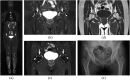

Results: STIR-WBMRI detected osteonecrosis in 15 (11.6%) patients. 38 joints were affected (mean, 2.5 per patient; range, 1-5 joints). Of the 38 joints affected by osteonecrosis, 33 had no clinical symptoms. Among the 12 patients who underwent regional MRI, STIR-WBMRI detected all 10 osteonecrotic sites seen on the regional MRI. The location, shape and size of the osteonecrotic lesions revealed on regional MRI were in accordance with those displayed on STIR-WBMRI. Of the 15 patients with osteonecrosis, 6 performed routine radiography of the affected joints and revealed no osteonecrotic lesions. Follow-up WBMRI detected new osteonecrosis in two patients whose first WBMRI revealed that there was no osteonecrosis in any skeleton.

Conclusion: In addition to displaying muscle inflammation, STIR-WBMRI can efficiently detect early multifocal osteonecrosis in the whole bodies of patients with PM/DM. Advances in knowledge: In patients with PM/DM, WBMRI which takes 12-15 min can display muscular involvement and detect early multisite osteonecrosis in the whole body at the same time. Osteonecrotic lesions revealed by WBMRI are in accordance with those displayed on regional WBMRI.